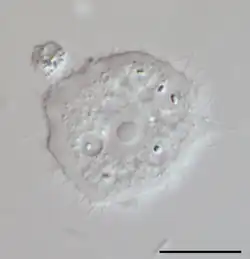

| Phase contrast micrograph of an Acanthamoeba polyphaga cyst. | |

Acanthamoeba is a genus of amoebae that are commonly recovered from soil, fresh water, and other habitats. Acanthamoeba has two evolutive forms, the metabolically active trophozoite and a dormant, stress-resistant cyst. Trophozoites are small, usually 15 to 25 μm in length and amoeboid in shape. In nature, Acanthamoeba species are free-living bacterivores, but in certain situations, they can cause infections (acanthamebiasis) in humans and other animals.[1]